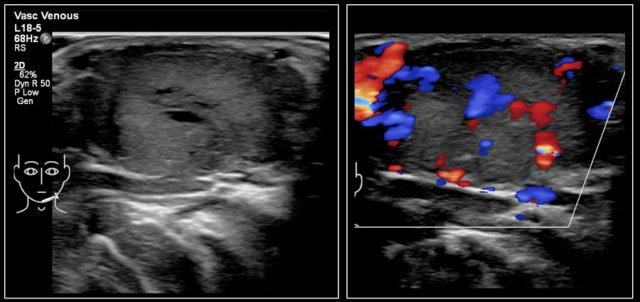

Một bé trai sáu tháng tuổi được phát hiện có khối sưng ở cổ bên trái ngay từ khi sinh ra.

Nhiều lần siêu âm không thể phân biệt được giữa u máu hay dị dạng tĩnh mạch.

Ở sáu tháng tuổi, siêu âm cho thấy một tổn thương chủ yếu cấu thành bởi các mạch máu, có kích thước tăng lên khi rặn.

Trên siêu âm Doppler màu, tổn thương cho thấy tăng lưu lượng máu khi khóc.

Chẩn đoán cuối cùng trên hình ảnh học và khám lâm sàng là dị dạng tĩnh mạch.